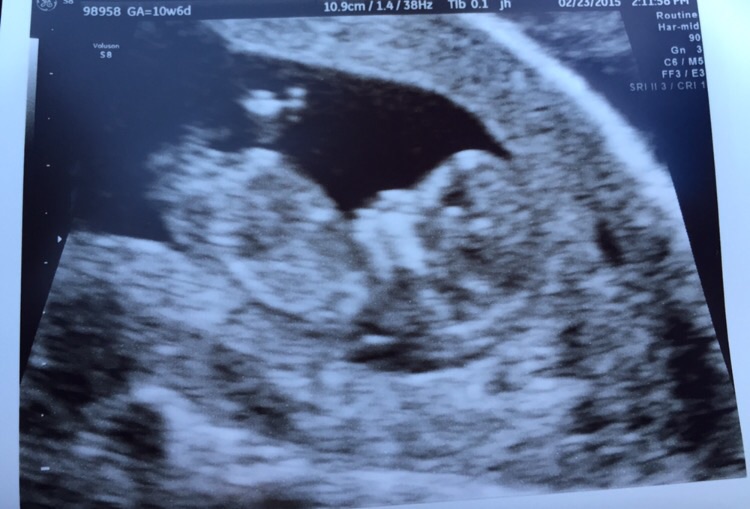

I had my first ultrasound last Wednesday. I went in thinking I was 9weeks 6days (this was based off my last cycle) but after they measured the baby they said I was 10weeks 6 days. I can't stop looking at my baby. I'm a FTM also.